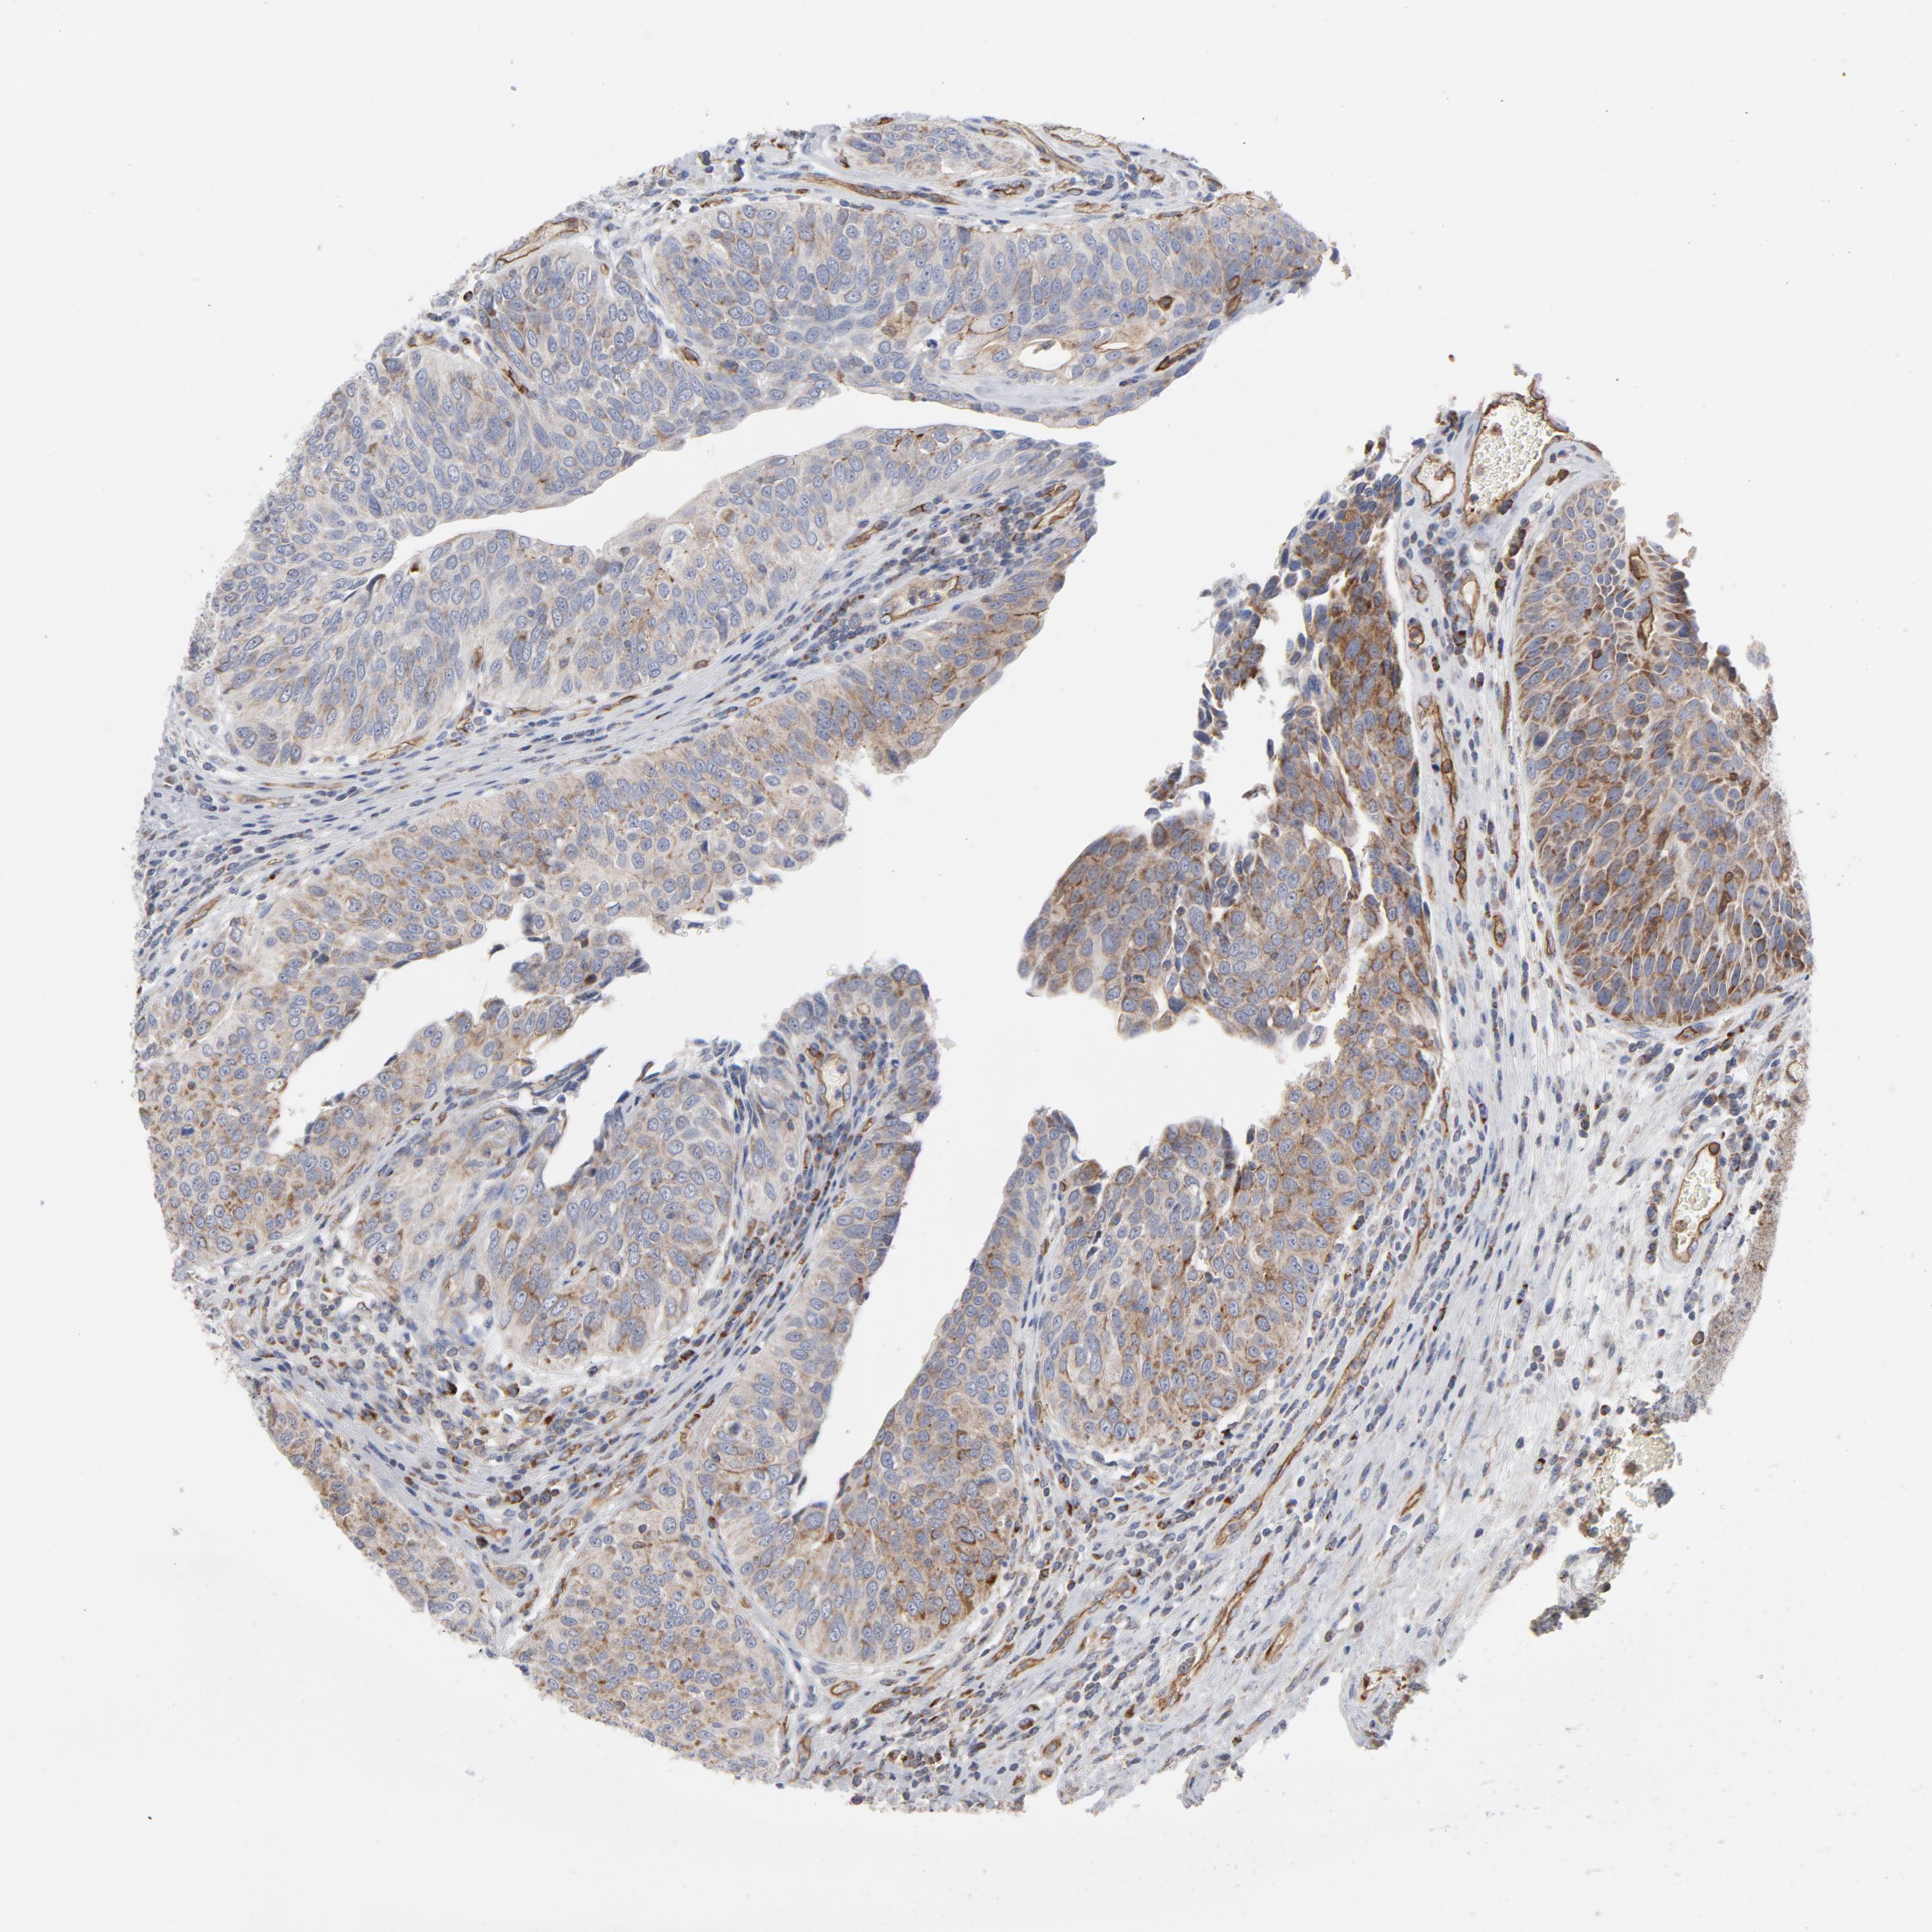

UROTHELIAL CANCER - Protein expressioni

A mouse-over function shows sample information and annotation data. Click on an image to view it in a full screen mode. Samples can be filtered based on level of antibody staining by selecting one or several of the following categories: high, medium, low and not detected. The assay and annotation is described here.

Note that samples used for immunohistochemistry by the Human Protein Atlas do not correspond to samples in the TCGA dataset.

Antibody stainingi

Antibody staining in the annotated cell types in the current human tissue is reported as not detected, low, medium, or high, based on conventional immunohistochemistry profiling in selected tissues. This score is based on the combination of the staining intensity and fraction of stained cells.

Each image is clickable and will lead to virtual microscopy that enables deeper exploration of all samples and also displays staining intensity scores, fraction scores and subcellular localization as well as patient and tissue information for each sample.

Antibody HPA003531

Staining

High

Medium

Low

Not detected

Intensity

Strong

Moderate

Weak

Negative

Quantity

>75%

75%-25%

<25%

None

Location

Nuclear

Cytoplasmic/membranous

Cytoplasmic/membranous,nuclear

Urothelial carcinoma, High grade

Urothelial carcinoma, Low grade